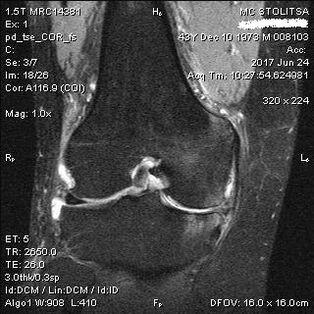

The diagnosis of arthrosis of the knee joint is carried out in the office of a rheumatologist or orthopedist.The doctor examines the affected joint, palpates it, listens to complaints and asks additional questions.Performs several tests - for example, asking the patient to bend their leg or take a few steps.Then, if it is necessary to clarify the stage of the disease or the nature of the pathological changes, he will refer you for additional research.For example, for computed tomography or radiography.